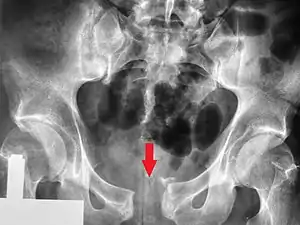

Pelvic fracture

Pelvic vertical shear fracture